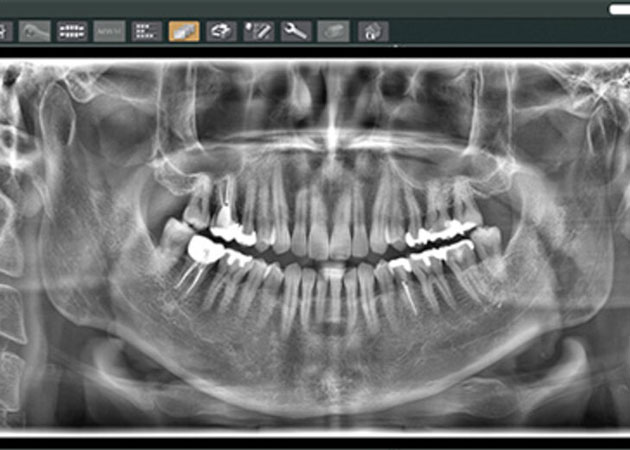

3. 03.検査・レントゲン

03.検査・レントゲン

カウンセリングの後、歯や歯ぐきの状態を詳しく確認するために、口腔内検査やレントゲン撮影を行います。レントゲンを使うことで、目に見えない部分や歯の内部まで詳しく確認でき、正確な診断が可能です。

※妊娠中の方はご相談ください。